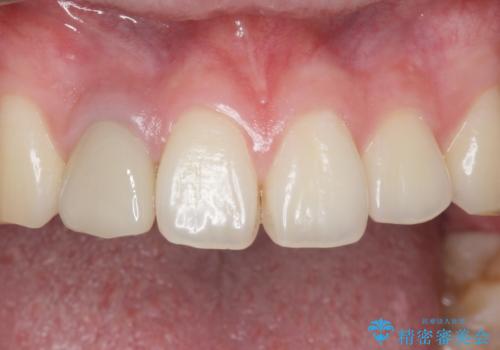

- 他院で入れたセラミッククラウンの色が気に入らないことを主訴に来院された患者様です。

高校生の時に部活で前歯をぶつけて神経が死んでしまい、歯が黒く変色したためセラミッククラウンで治療したとのことでした。

精査したところ、透過性のあるセラミッククラウンで治療されており、内側の黒い土台が透けてクラウンが黒ずんで見えていました。